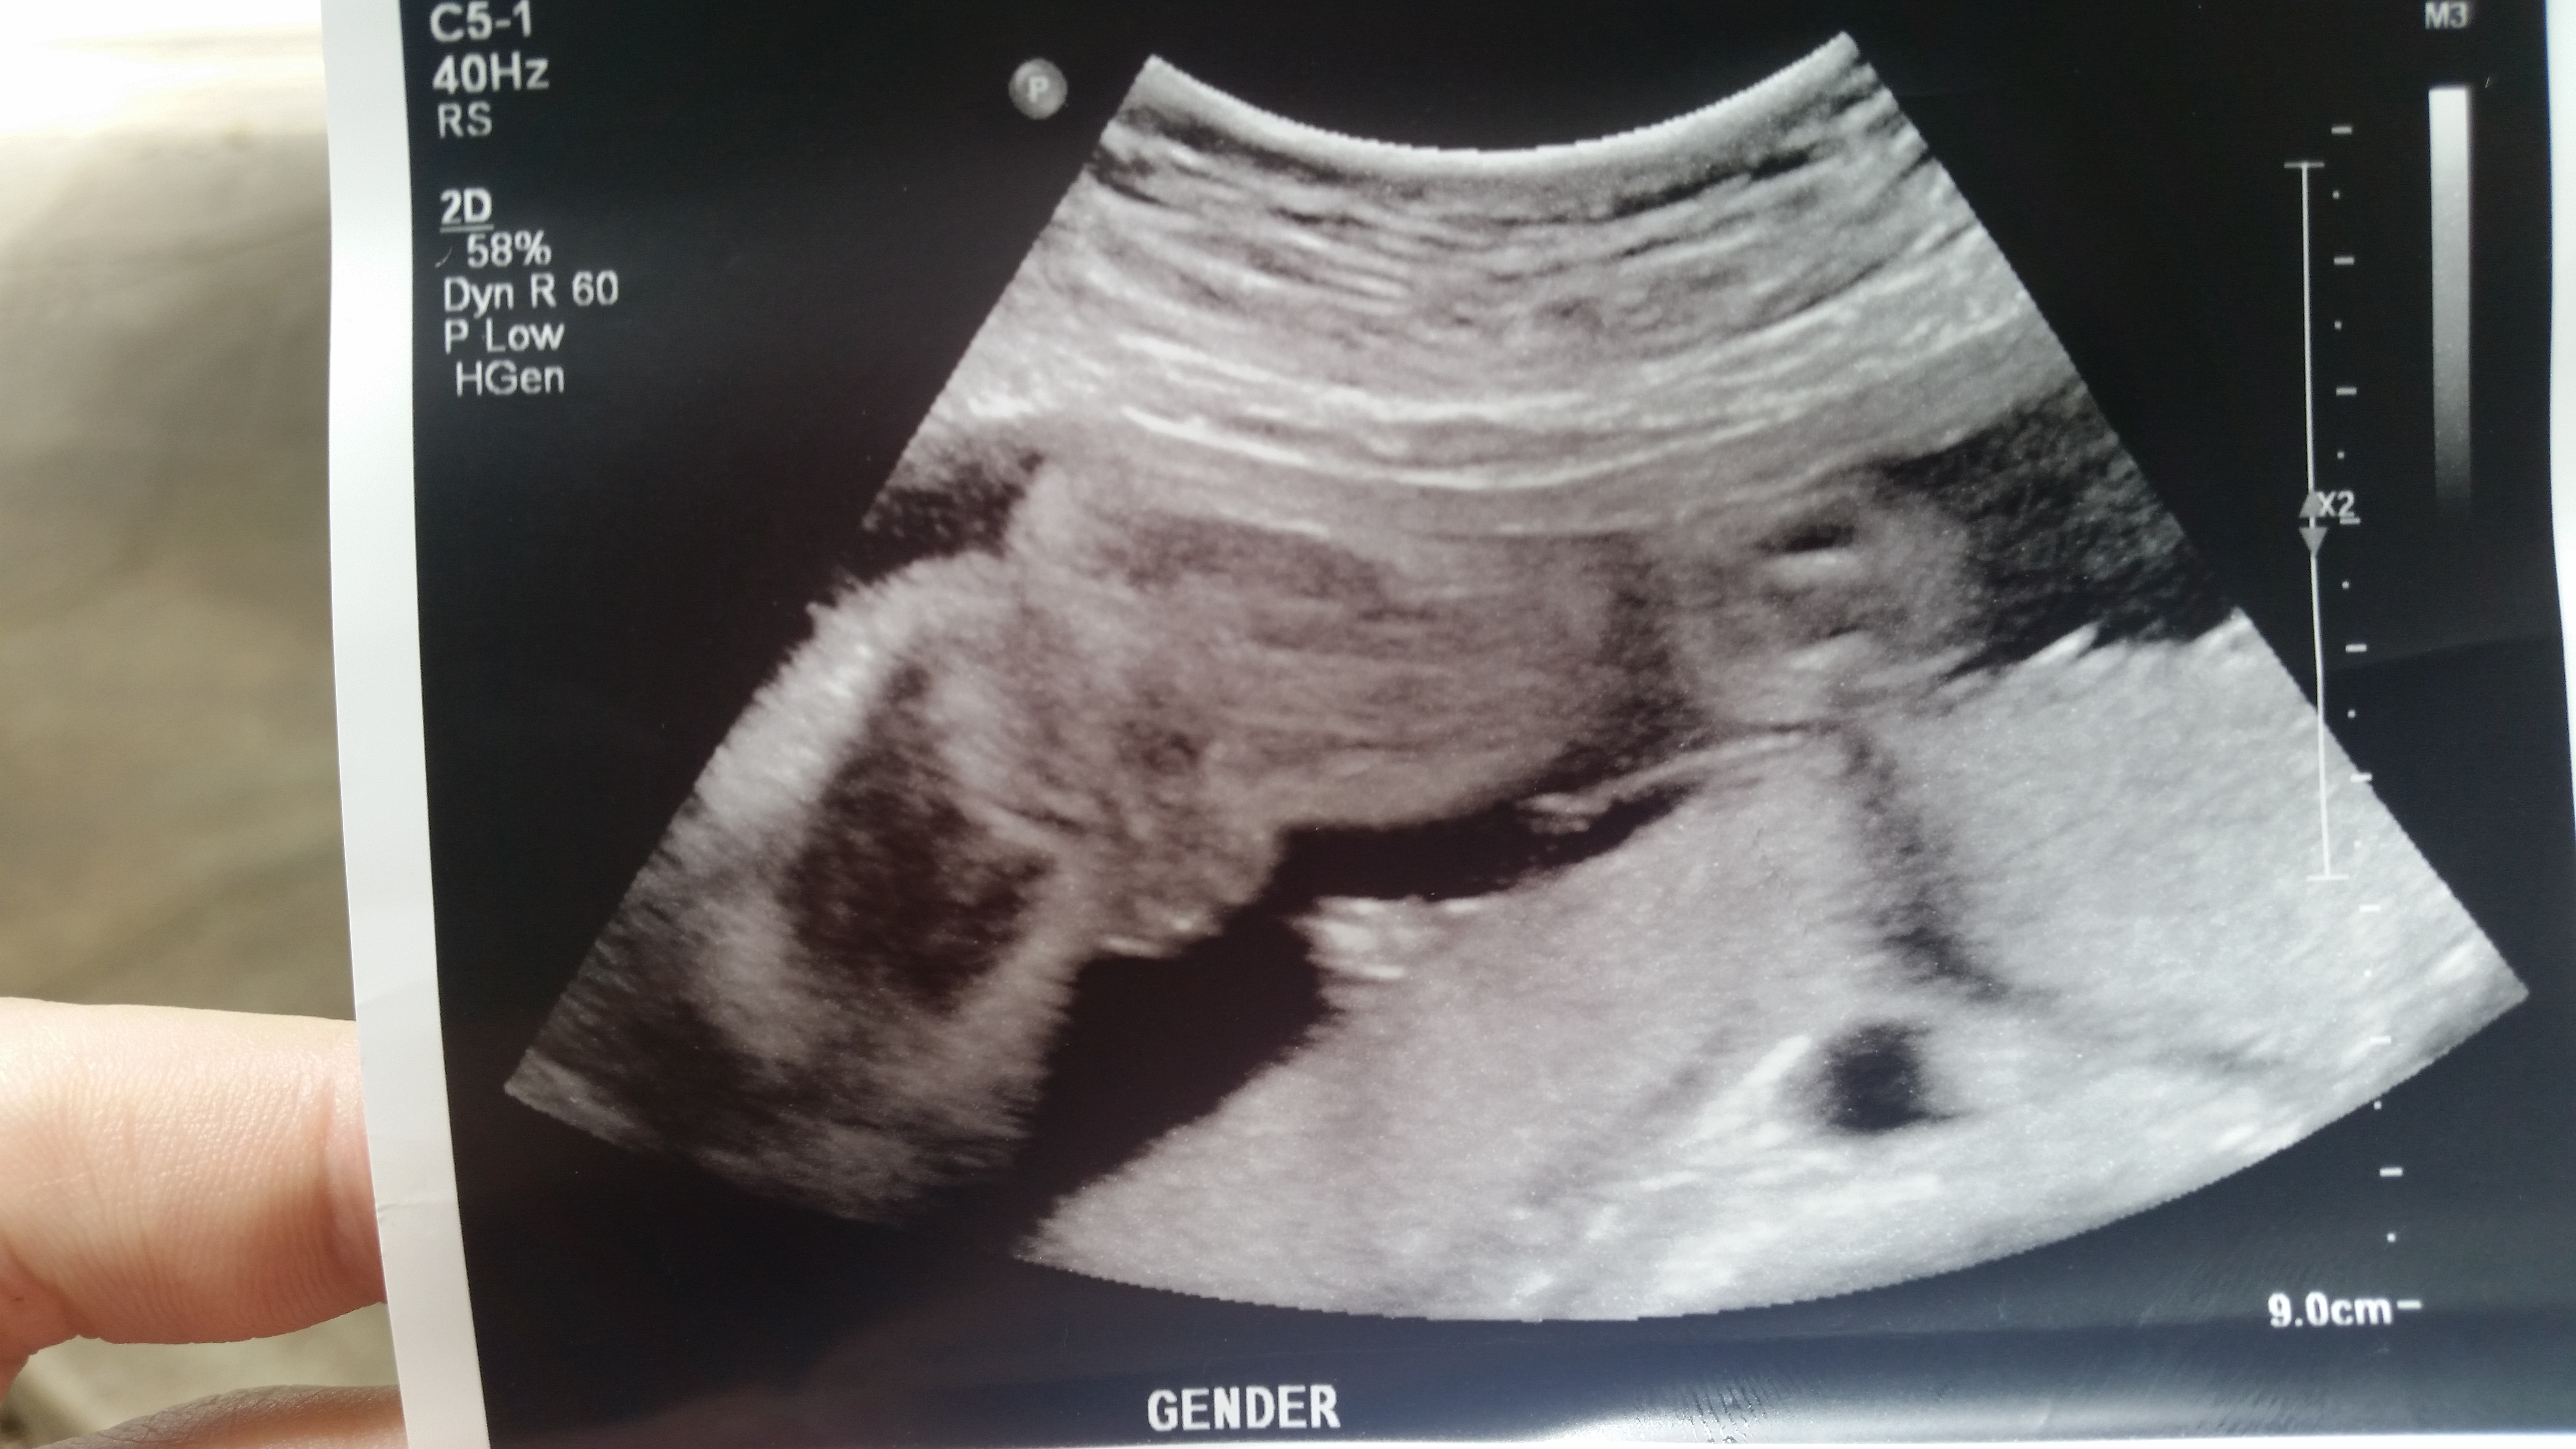

Update i just had my 25 week a 1 day scan please scroll down for latest pics.

I went for my 20 week scan today and came out a bit disappointed I was not provided any potty shots to take they would only give me these 2 pics. The lady did say she thinks it's a girl but can't confirm and based on her inexperience I'm skeptical to say the least .